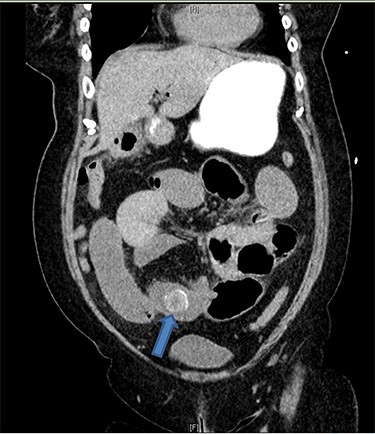

There were associated vomiting and abdominal distension. Her last bowel movement was 12 hours prior to the presentation, and she passed minimal flatus since. She has a background of chronic kidney disease. She was slightly tachycardic in ED. Abdominal examination demonstrated a mildly distended and soft abdomen with left lower quadrant tenderness without peritonism. Blood work showed an acute on chronic renal failure (creatinine 198 μmol/l and estimated glomerular filtration rate 24 ml/min/1.73 m2). Liver function tests were mildly deranged (bilirubin 27 μmol/l, alkaline phosphatase 105 U/l, GGT 85 U/l, alanine aminotransferase 38 U/l, aspartate aminotransferase 37 U/l) and white cell count was slightly elevated (10.7 × 109/l; reference range 3.7–9.5 × 109/l). Computed tomography (CT) scan (Figs 1 and 2) demonstrated multiple loops of moderated dilated small bowel. There were two 25-mm gallstones in a loop of small bowel in the right lower quadrant. The gallbladder is collapsed with intraluminal gas. There was pneumobilia in the biliary tree. The features on CT are in keeping with a gallstone ileus. Initial management included fluid resuscitation, insertion of a nasogastric tube, analgesia and nil by mouth. A Foley catheter was inserted to monitor urine output. A laparotomy proceeded within 24 hours. Two palpable gallstones were found within the distal ileum. A longitudinal enterotomy was made immediately proximal to the point of calculus impaction and two calculi were delivered from the bowel lumen (Fig. 3). There was a suspected calculus contained within the gallbladder. However, the decision was made not to proceed for further reduction via the fistula due to significant risk of duodenal injury. Her recovery was uneventful, and renal function returned to baseline. She was discharged home 7 days after her operation. During the outpatient clinic follow-up, an interval cholecystectomy and cholecystoduodenal fistula closure had been arranged in 4–6 months after her initial operation.

Coronal CT image demonstrates gallstones (blue arrow) (only one gallstone shown on this image) in a loop of small bowel in the right lower quadrant.